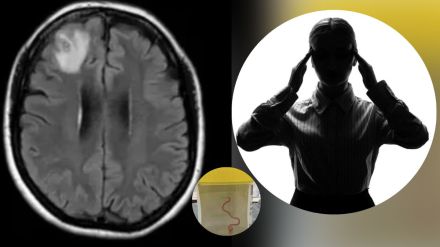

२०२२ मध्ये या महिलांमध्ये नैराश्य आणि विस्मरणाची लक्षणेही दिसू लागली. त्यानंतर डॉक्टरांनी तिच्या मेंदूचे एमआरआय स्कॅन केले, ज्यामध्ये डॉक्टरांना काही गडबड आढळून आली. त्यानंतर त्यांनी महिलेला शस्त्रक्रिया करण्याचा सल्ला दिला.शस्त्रक्रिया केल्यानंतर महिलेत्या मेंदूत एक जिवंत अळी असल्याचं उघडकीस आलं. न्यूयॉर्क पोस्टने द गार्डियनच्या हवाल्याने लिहिलं, कैनबरा येथील संसर्गजन्य रोग विशेषज्ञ डॉ. संजय सेनानायके म्हणाले, “न्यूरोसर्जनने शस्त्रक्रिया केली नाही कारण त्यांना महिलेच्या मेंदूमध्ये एक फिरणारी जिवंत अळी आढळली.”

सर्जिकल टीमला ३ इंच लांबीची, चमकदार लाल, परजीवी राउंडवर्म सापडली ज्याला शास्त्रज्ञ ओफिडास्कॅरिस रॉबर्टसी म्हणून ओळखतात. महिल्याच्या मेंदूतील ती रेंगाळत होती. शिवाय त्याचं माणसाच्या शरीरात सापडणं धक्कादायक होतं कारण ती सामान्यतः सापांमध्ये आढळते. राउंडवर्मचा हा विशिष्ट प्रकार कार्पेट पायथन्समध्ये आढळतात, जी कंस्ट्रक्टरची एक मोठी प्रजाती असून त्या ऑस्ट्रेलिया, इंडोनेशिया आणि पापुआ न्यू गिनीमध्ये आढळतात.